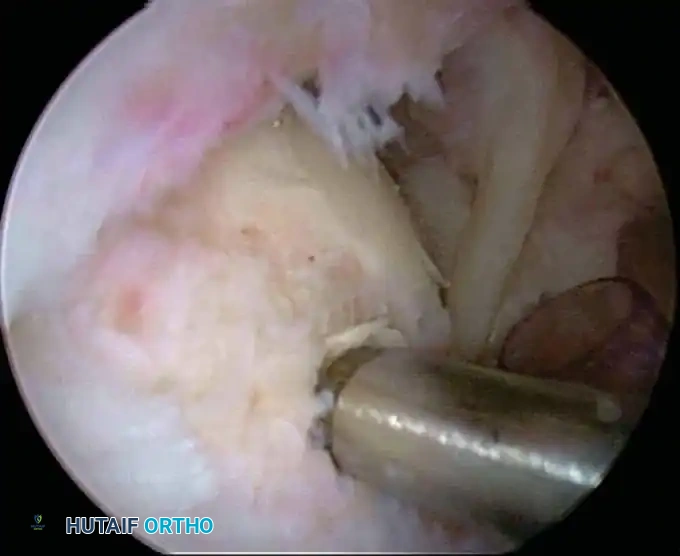

Once diagnostic evaluation is complete and hemostasis is secured, the therapeutic phase commences. Whether performing a SLAP repair, a Bankart stabilization, or a rotator cuff repair, the principles of tissue mobilization, anatomical footprint restoration, and secure biomechanical fixation remain paramount.

Modern arthroscopy relies heavily on suture anchors (biocomposite or all-suture constructs) and advanced arthroscopic knot-tying or knotless techniques. The ability to pass sutures through retracted, fibrotic tissue and secure them under appropriate tension without strangulating the microvascular supply is the hallmark of a master arthroscopist.